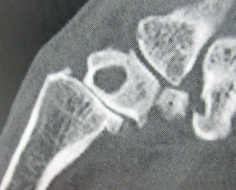

A CT scan may be requested if there is any uncertainty as to the quality of the bonestock, especially if there is any suspected osteolysis that could jeopardise the proposed surgery. Figure 1. There are three types of basal thumb osteoarthritis (Figures 2 to 4):